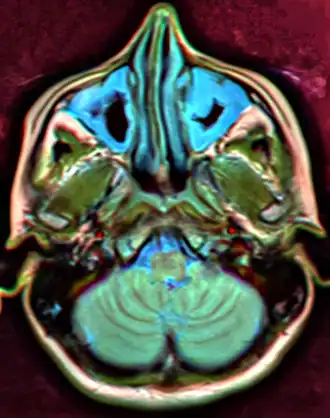

-

MRI image showing sinusitis. Edema and mucosal thickening appear in both maxillary sinuses. -